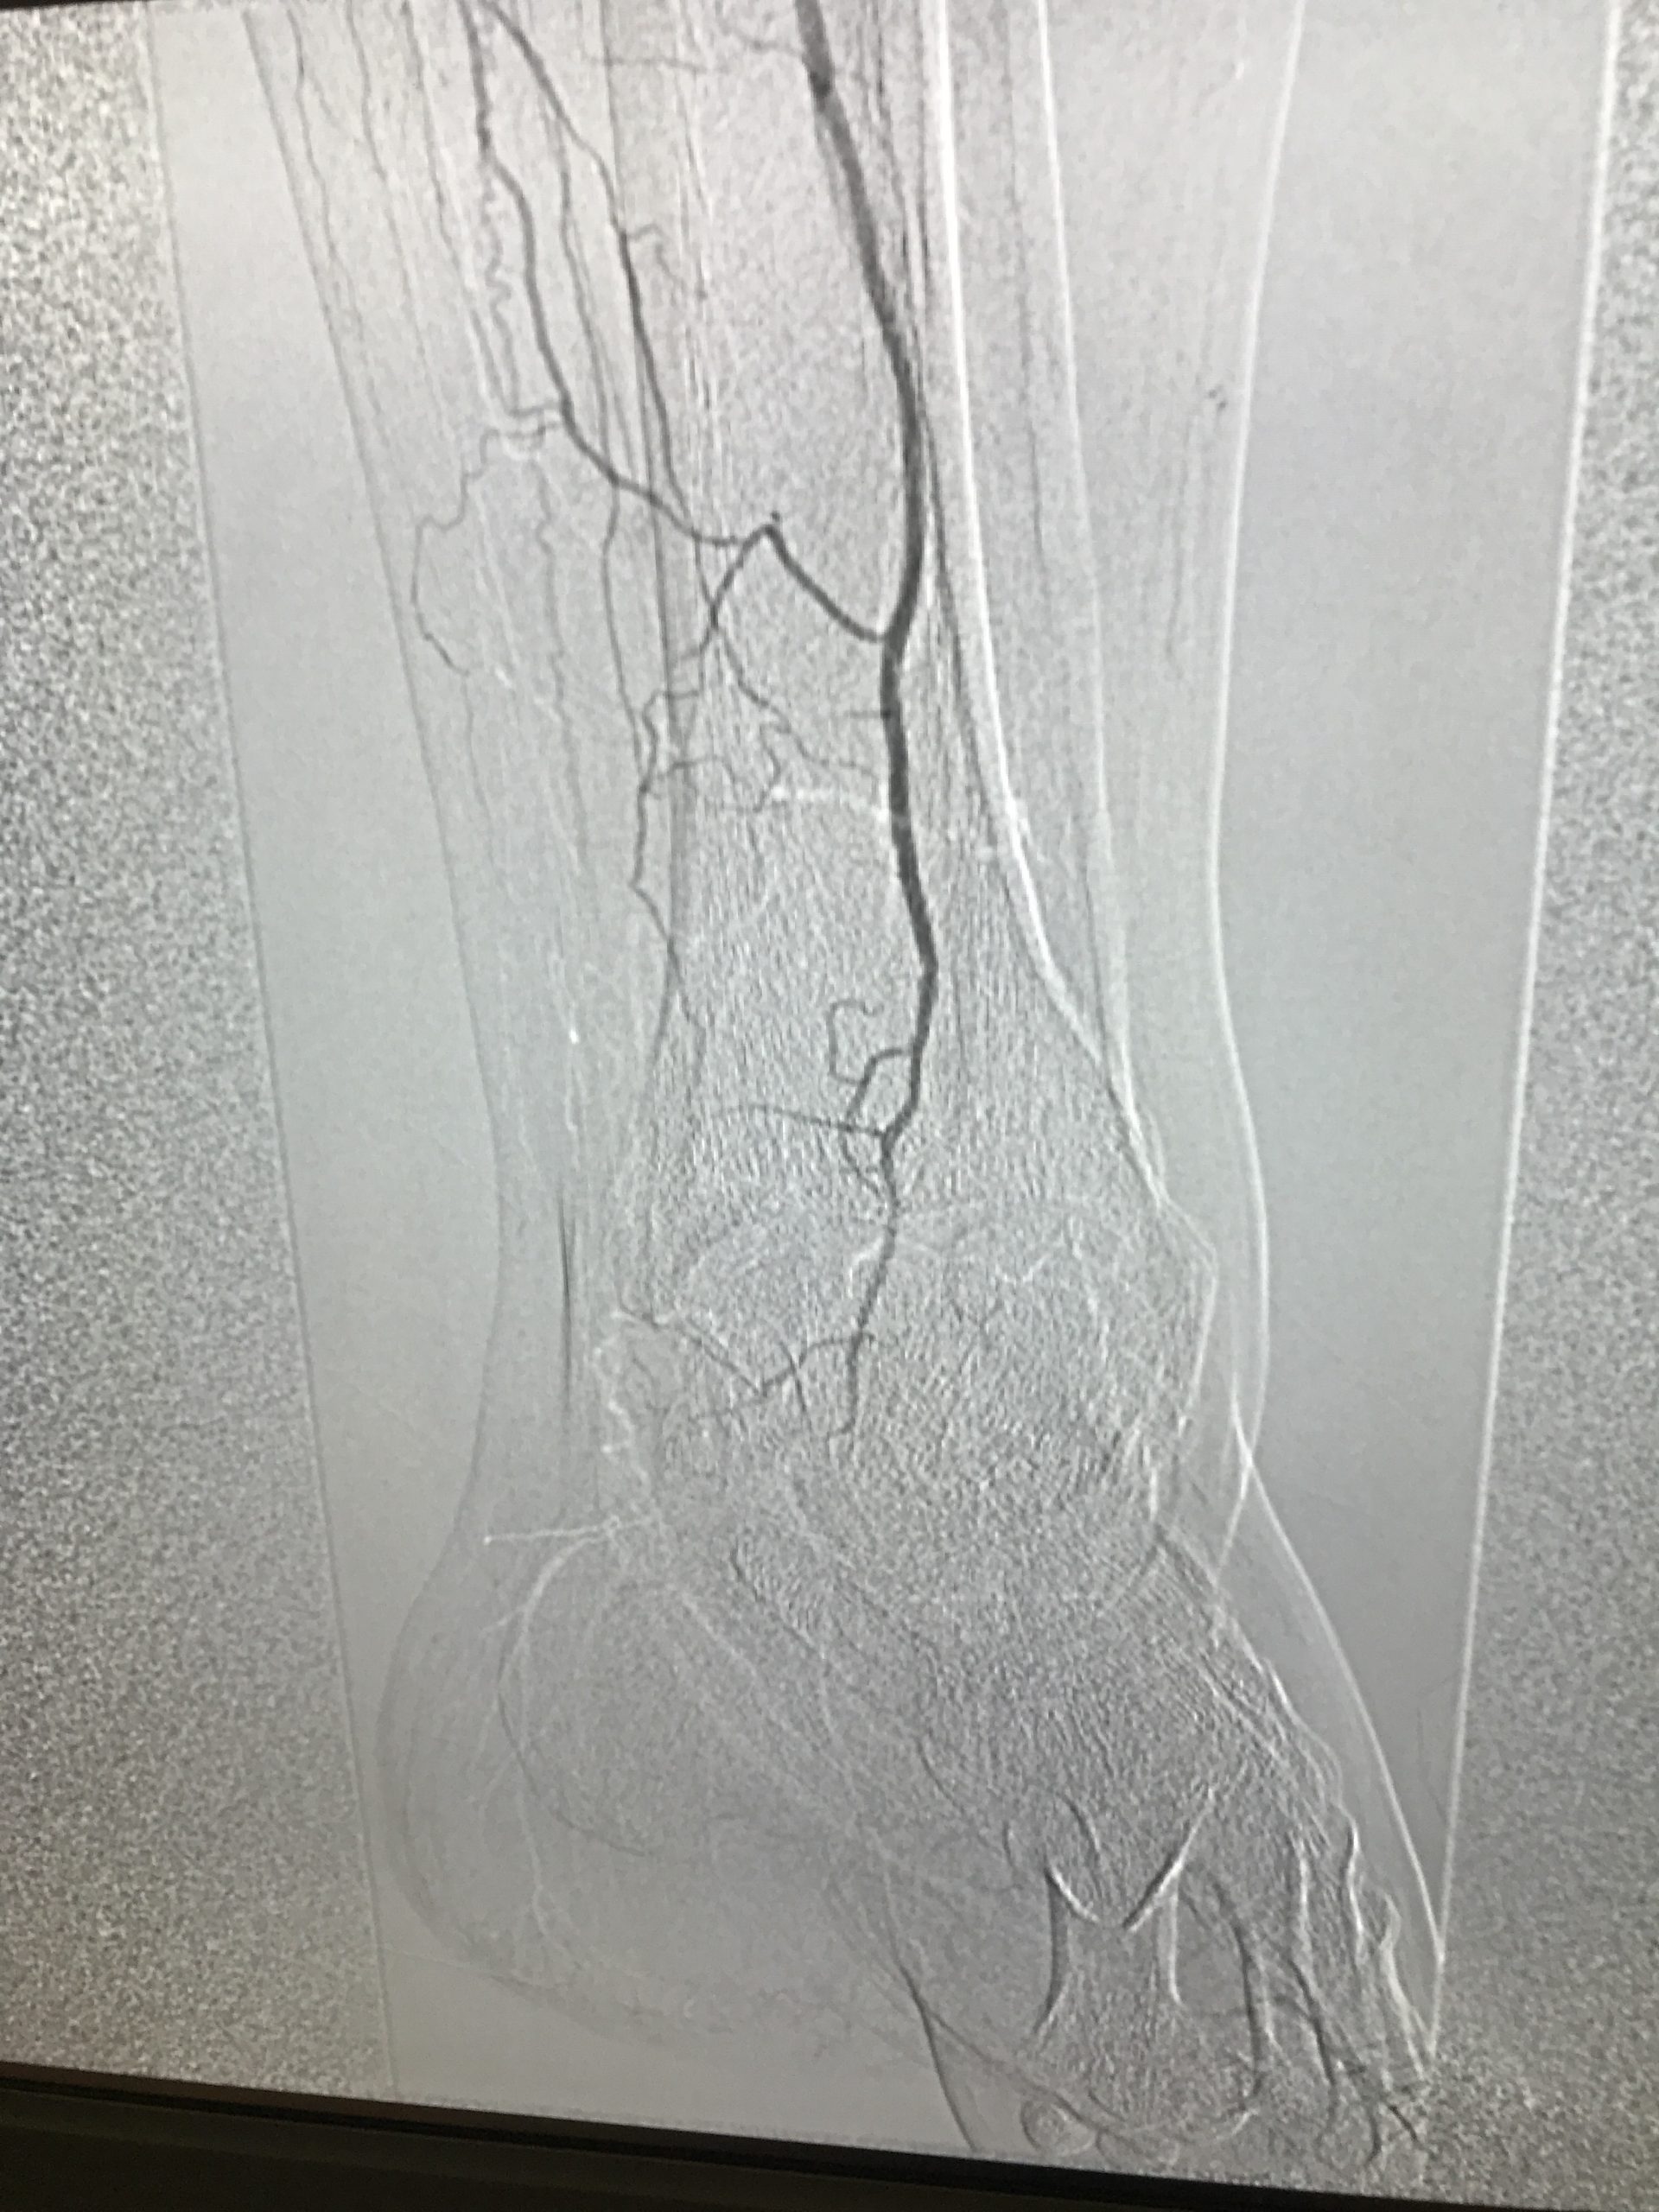

Manual de Cirugía Vascular Cap 10 Pie diabético Pie Diabetico Cirugia Vascular El pie diabético (pd) es una de las complicaciones más graves de la diabetes mellitus (dm). La valoración vascular del pie diabético no es sencilla en tanto en cuanto no solo se ve influida por el. Cuando un paciente diabético tiene una úlcera infectada en el pie, la primera preocupación debería ser el control de la infección. Servicio para la. Pie Diabetico Cirugia Vascular.

Pie diabético Centro Vascular de Alta Especialidad Angiología, Cirugía Vascular y Endovascular Pie Diabetico Cirugia Vascular Identificar el nivel de conocimiento, actitud y práctica orientada a la prevención del pie diabético en personas ingresadas o sus cuidadores principales en la unidad de cirugía vascular. El pie diabético (pd) representa una de las complicaciones crónicas de la enfermedad diabética, que se debe a alteraciones estructurales y funcionales del pie, lo que. Cuando un paciente diabético tiene una. Pie Diabetico Cirugia Vascular.

Pie Diabético con Angiopatía Examen Vascular y Cuando Derivar a Cirugía Vascular ANAMyS Pie Diabetico Cirugia Vascular Servicio para la atención del paciente con pie diabético, lo que más frecuentemente se realiza es la debridación y lavados quirúrgico, en la. Identificar el nivel de conocimiento, actitud y práctica orientada a la prevención del pie diabético en personas ingresadas o sus cuidadores principales en la unidad de cirugía vascular. El pie diabético (pd) es una de las complicaciones. Pie Diabetico Cirugia Vascular.

Papel del cirujano vascular en el pie diabético FONDOSCIENCE Pie Diabetico Cirugia Vascular Identificar el nivel de conocimiento, actitud y práctica orientada a la prevención del pie diabético en personas ingresadas o sus cuidadores principales en la unidad de cirugía vascular. Cuando un paciente diabético tiene una úlcera infectada en el pie, la primera preocupación debería ser el control de la infección. La valoración vascular del pie diabético no es sencilla en tanto. Pie Diabetico Cirugia Vascular.